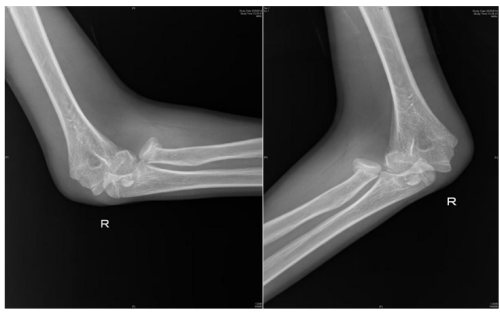

术前检查提示桡骨头骨折,肱骨远端骨折,肘关节脱位

近日,13岁的邓佑(化名)在放学途中,一边看手机一边走路,未留意前方障碍,整个人猛地撞上了护栏,在倒地的瞬间,他用右手撑地,随即感到一阵钻心的剧痛从肘部爆发开来,被紧急送往香港马会app (南华大学附属香港马会app )手足显微外科就诊。经系统检查,被诊断为:右桡骨头骨折、肱骨内上髁骨折、右肘关节脱位。

“患者入院后,我们紧急行右肘关节脱位复位,肿胀消退后为其设计了尽可能微创的手术方案:右桡骨头骨折闭合复位弹性髓内针内固定+肱骨内上髁骨折切开复位内固定,手术顺利。术后患者恢复良好,即将出院。”据该院手足显微外科主任、副主任医师蒋亮东介绍,医院经常接诊因低头看手机导致意外受伤的患者。其中,桡骨头骨折在青少年人群中尤为常见,它通常是由于在摔倒时手掌撑地,间接暴力传导至肘部而发生的骨折。

人体的肘关节就像一座精密的“协作工厂”,里面住着三位重要“伙伴”—桡骨、尺骨和肱骨。桡骨顶端有一个像“小圆帽”的结构,那就是桡骨头。它相当于肘关节的“旋转轴承”,帮助我们完成转笔、拧瓶盖、拧毛巾等需要前臂旋转的动作。蒋亮东提醒,当我们低头紧盯手机屏幕,不仅注意力高度集中,身体平衡能力也会下降。一旦不慎跌倒,手会本能地支撑地面。此时巨大冲击力会沿手臂向上传导,如同“冲击波”一般直击桡骨头这个“小圆帽”,轻则使其裂缝,重则崩碎成数块。通过X光片,医生可以清晰地看到它的“受伤模样”。